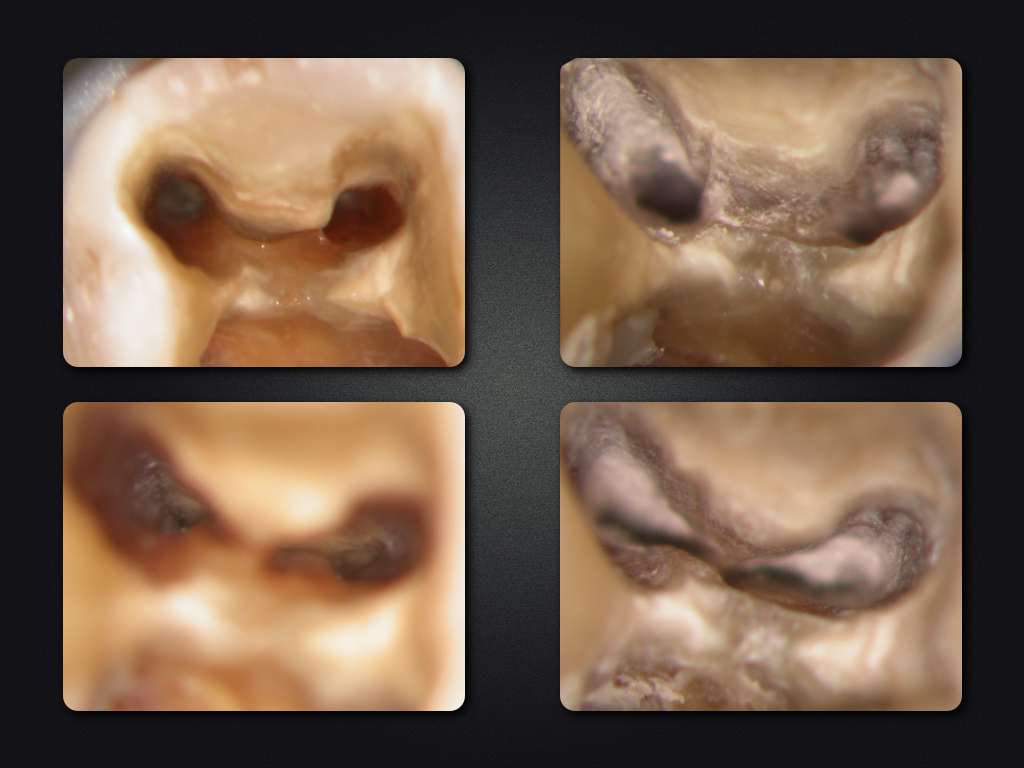

36D.002

WSR ohne WF